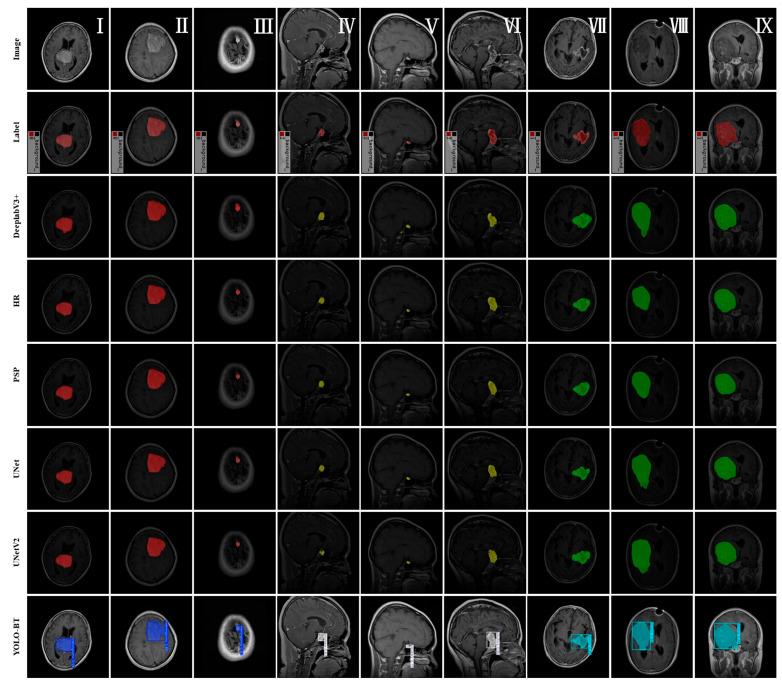

使用YOLO-BT对MRI图像进行高效脑肿瘤分割

Efficient Brain Tumor Segmentation for MRI Images Using YOLO-BT.

Aiming at the problems of inaccurate segmentation and low detection efficiency caused by irregular tumor shape and large size differences in brain MRI images, this study proposes a brain tumor segmentation algorithm, YOLO-BT, based on YOLOv11. YOLO-BT uses UNetV2 as the backbone network to enhance the feature extraction ability of key regions through the attention mechanism. The BiFPN structure is introduced into the neck network to replace the traditional feature splicing method, realize the two-way fusion of cross-scale features, improve detection accuracy, and reduce the amount of calculations required. The D-LKA mechanism is introduced into the C3k2 structure, and the large convolution kernel is used to process complex image information to enhance the model's ability to characterize different scales and irregular tumors. In this study, multiple sets of experiments were performed on the Figshare Brain Tumor dataset to test the performance of YOLO-BT. The data results show that YOLO-BT improves Precision by 2.7%, Recall, mAP50 by 0.9%, and mAP50-95 by 0.3% in the candidate box-based evaluation compared to YOLOv11. In mask-based evaluations, Precision improved by 2.5%, Recall by 2.8%, mAP50 by 1.1%, and mAP50-95 by 0.5%. At the same time, the mIOU increased by 6.1%, and the Dice coefficient increased by 3.6%. It can be seen that the YOLO-BT algorithm is suitable for brain tumor detection and segmentation.

针对脑磁共振成像(MRI)图像中肿瘤形状不规则、大小差异大导致分割不准确和检测效率低的问题,本研究提出了一种基于YOLOv11的脑肿瘤分割算法YOLO - BT。YOLO - BT使用UNetV2作为主干网络,通过注意力机制增强关键区域的特征提取能力。将BiFPN结构引入颈部网络以取代传统的特征拼接方法,实现跨尺度特征的双向融合,提高检测精度并减少所需的计算量。将D - LKA机制引入C3k2结构,使用大卷积核处理复杂图像信息,以增强模型表征不同尺度和不规则肿瘤的能力。在本研究中,对Figshare脑肿瘤数据集进行了多组实验,以测试YOLO - BT的性能。数据结果表明,与YOLOv11相比,在基于候选框的评估中,YOLO - BT的精确率提高了2.7%,召回率、mAP50提高了0.9%,mAP50 - 95提高了0.3%。在基于掩码的评估中,精确率提高了2.5%,召回率提高了2.8%,mAP50提高了1.1%,mAP50 - 95提高了0.5%。同时,交并比(mIOU)提高了6.1%,骰子系数提高了3.6%。可见,YOLO - BT算法适用于脑肿瘤检测与分割。